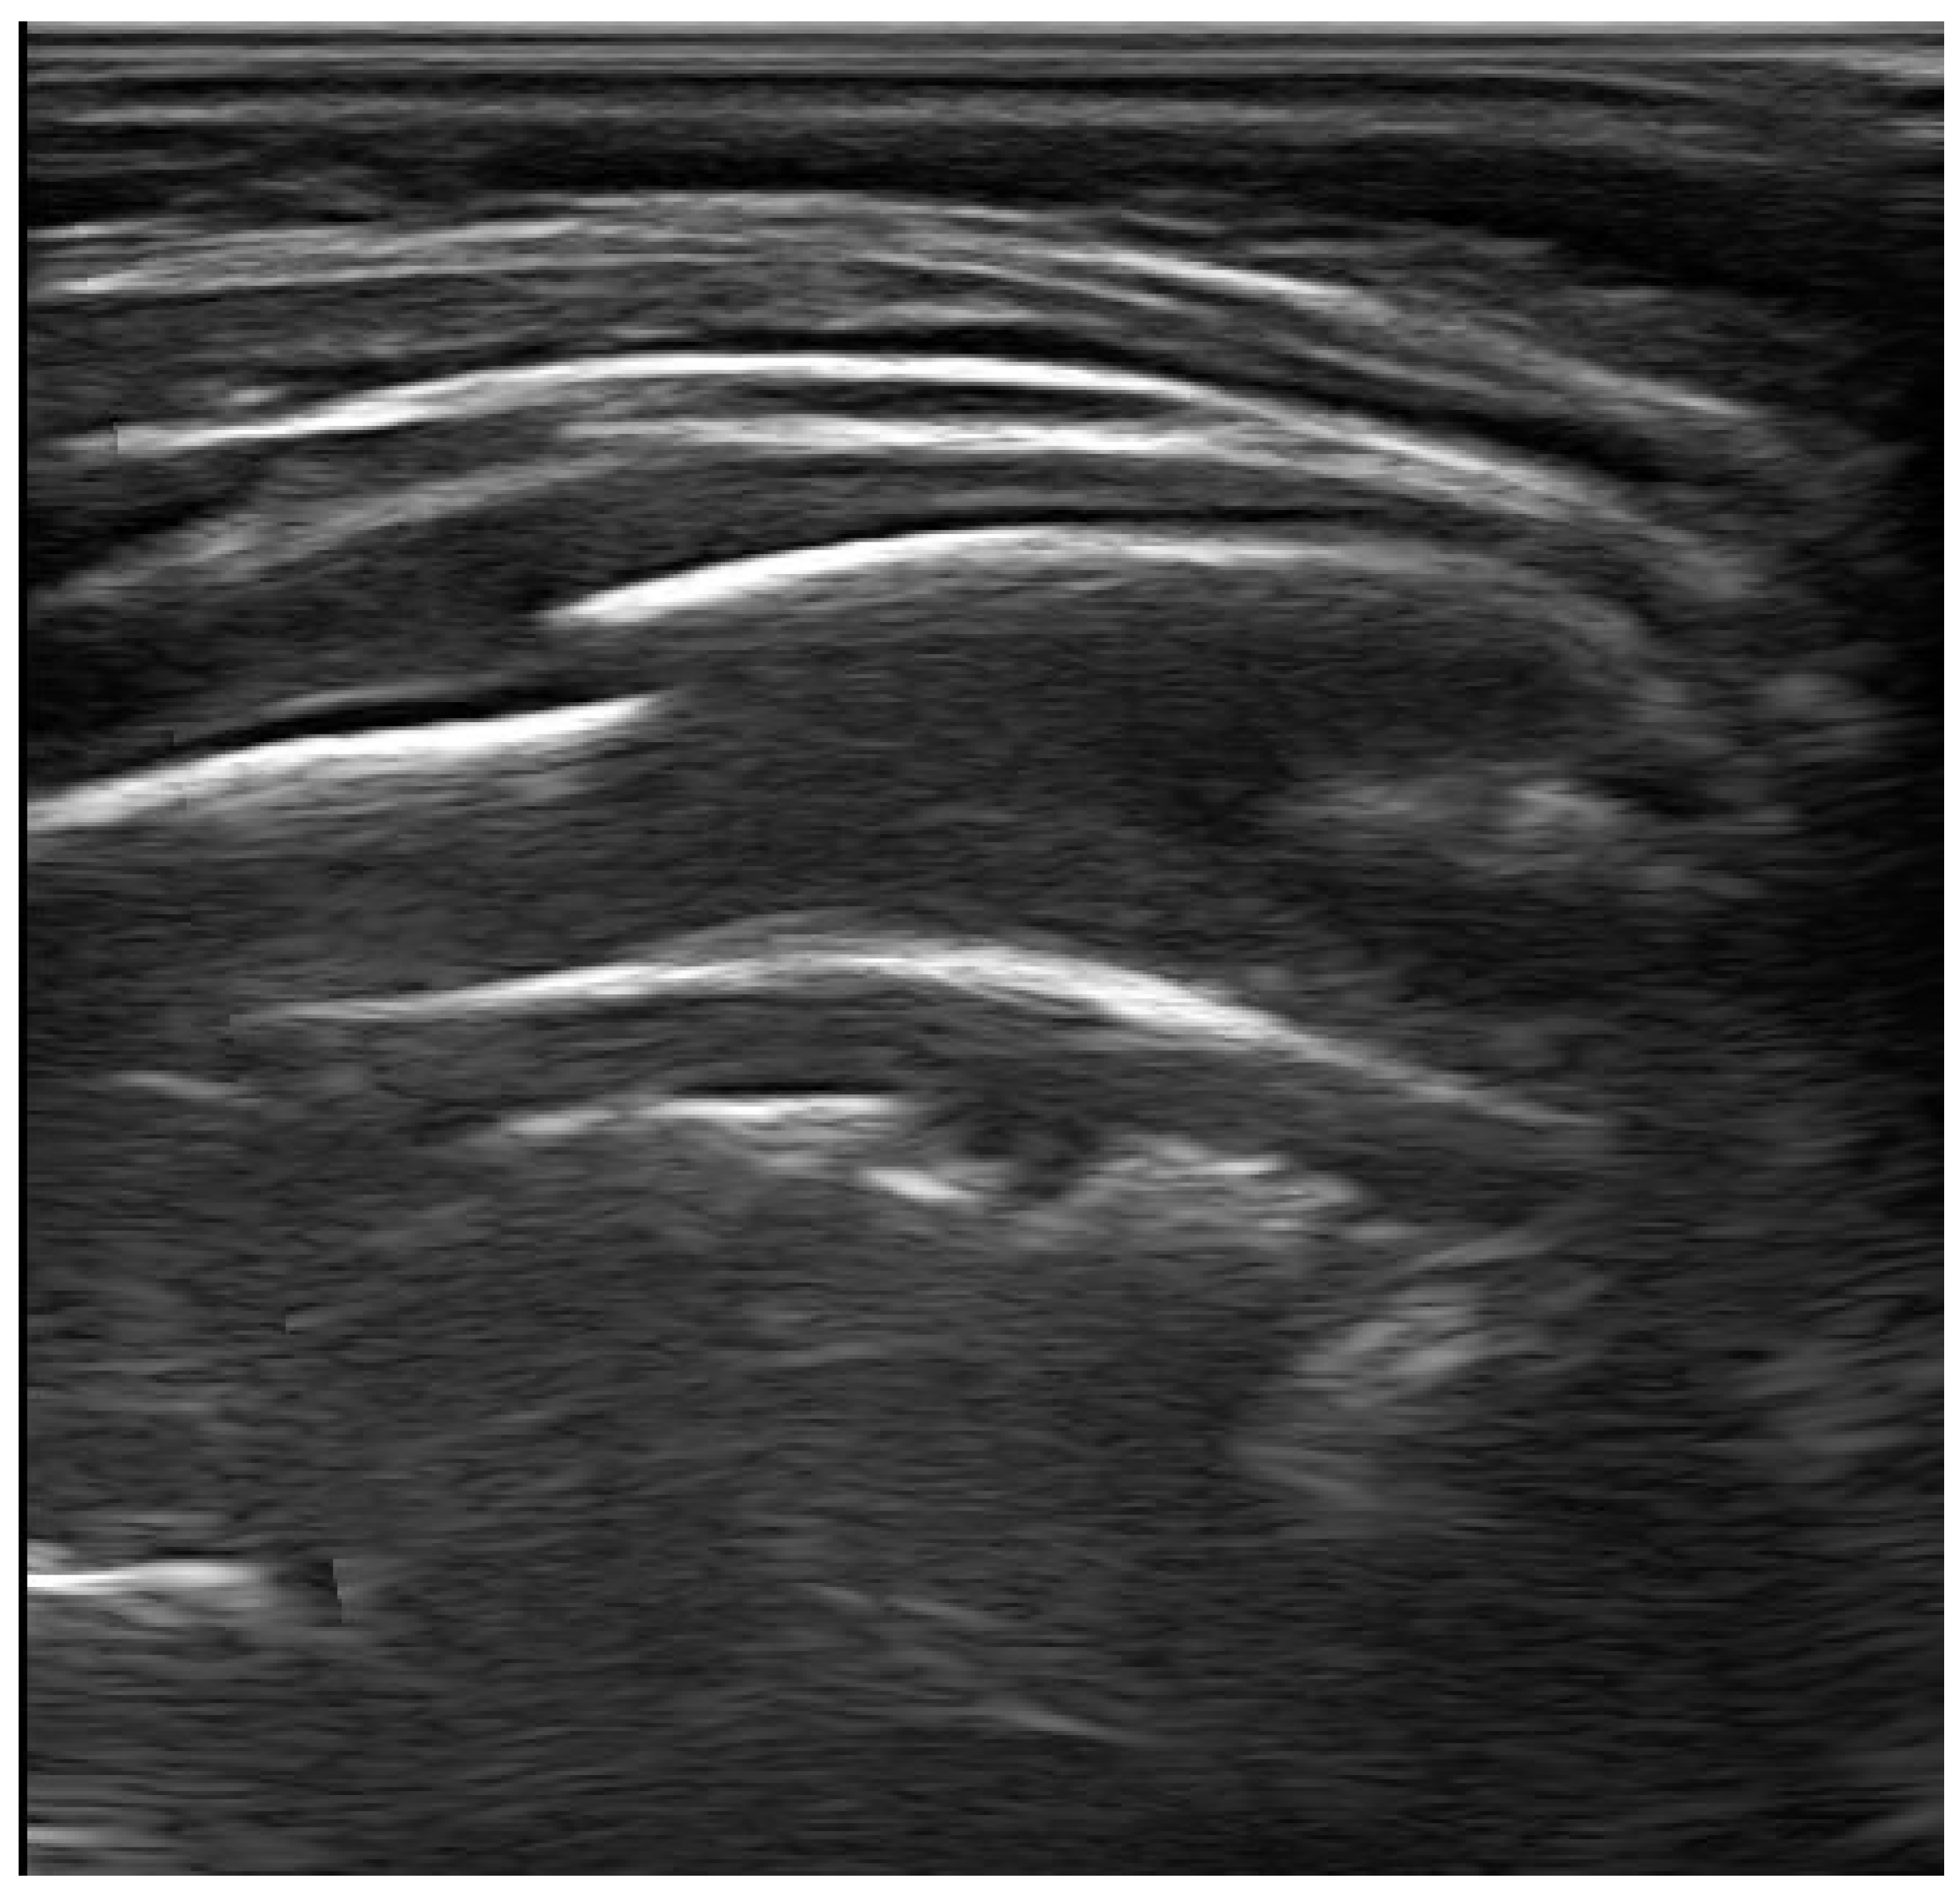

2. Examination Technique and Ultrasound Characteristics in Healthy Subjects

4.2. Pneumonia